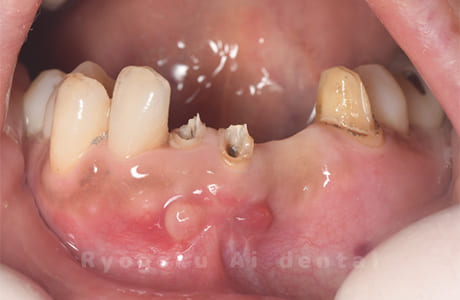

部分矯正クラウンレングスニング正面術前

-

部分矯正クラウンレングスニング正面術中

部分矯正クラウンレングスニング正面術後

- 原因

- パーフォレーション、慢性根尖性歯周炎

- 治療内容

- マイクロエンド、MTM、クラウンレングスニング、歯根端切除術

- 治療費用

- 286,000円

他院で歯の根の中に穴が空いているとのことで抜歯と診断された患者様です。一部穴が空いている部分を修復し、部分矯正を行い、手術を行いました。経過良好で、患者様も満足されています